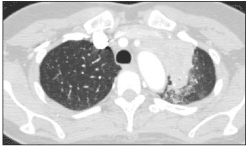

Laboratory analysis revealed a white blood cell count of 3400/µL, with 80% neutrophils and 12% lymphocytes; a hematocrit of 28% with normal platelet count; albumin, 2.9 g/dL; and serum protein, 7.7 g/dL. A chest radiograph revealed a left upper lobe infiltrate (Figure 1). A chest CT scan further characterized this apical infiltrate as a mass-like consolidation with associated lymphadenopathy (Figure 2).

Figure 2.CT scan with contrast showing mass-like consolidation at the anterior aspect of the left lung apex, with central areas of low attenuation consistent with necrosis. Contiguous with this mass-like consolidation is confluent lymphadenopathy in the aorticopulmonary window (not pictured). There are also innumerable subcentimeter low-attenuation lesions throughout the spleen, which are of indeterminate etiology (not pictured). (Illustration courtesy of the department of radiology, New York Presbyterian Hospital–Weill Medical College of Cornell University, New York.)